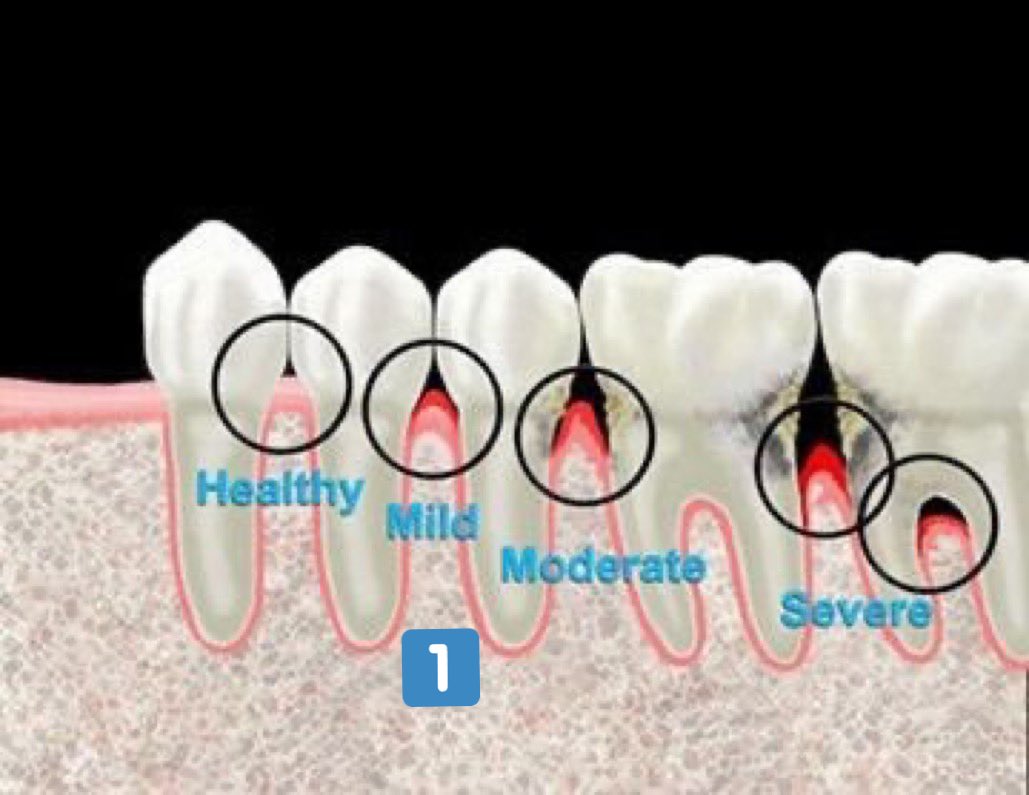

مراحل التهاب اللثة:

التهاب اللثة الخارجي(مرحلة١):

- الانتفاخ

-الإحمرار

-النزف من اللمس او التفريش

-الألم وتختلف درجته من شخص لآخر

-سهل العلاج ويختفي تماماً بإزالة المسبب والعناية بنظافة الاسنان والاهتمام وعدم إهمال الخيط السني

التهاب اللثة العميق(مرحلة٢):

-تآكل بسيط في اطراف العظم الداعم للآسنان وقد(غالبا)يكون مصحوب بعلامات من التهاب اللثة الخارجي

اعراضه قد تشابه المرحلة (١) وقد لا يكون ظاهرا

-يمكن علاجه إذا اكتشف باكرا وإيقاف تقدمه.

المرحلة المتقدمة من التهاب اللثة (المرحلة ٤):

-ألم ونزف

-حركة واضحة ومؤلمة عند المضغ

-رائحة كريهة ومزعجة

-سقوط الأسنان بدون التعرض لضربات أو حوادث

-العلاج قد يكون غير ممكن 💔